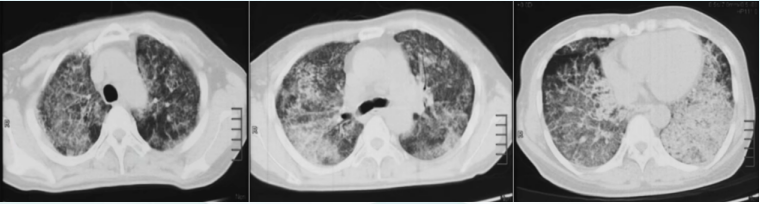

9年前(2014年),患者呼吸困难逐渐加重,不能爬山或剧烈活动,爬2层楼梯后自觉憋气,伴咳嗽、咳痰加重,晨起为著,无发热、咯血、胸痛。再次就诊于北京某三甲医院,动脉血气分析(2014-08-27,未吸氧):pH 7.41,PaCO2 35.5 mmHg,PaO2 49.1 mmHgSaO2 82.4%;胸部CT示:双肺野可见弥漫性斑片状高密度影,部分呈铺路石样改变(图2);肺功能示:限制性通气功能障碍伴弥散功能减低(表1)2014年9月22日行全麻下全肺灌洗术,双肺均灌洗生理盐水10000 ml,分别回收淘米水样灌洗液10300 ml(左肺)及10750 ml(右肺),术后呼吸困难症状好转不明显,鼻导管吸氧5 L/min时,指脉氧饱和度可维持95%左右。出院后规律门诊随访,呼吸困难症状未减轻,需氧疗,加用粒细胞-巨噬细胞集落刺激因子(GM-CSF)150 μg 2次/日(用1周、停1周)雾化吸入治疗数月,患者症状略改善。

图片

2  患者2014年9月胸部CT